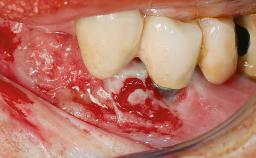

Peri-implantitis Resulting in Bisphosphonate-related Osteonecrosis of the Jaw

A 82-year-old female patient was referred to the Department of Oral Surgery and Stomatology at the University of Bern, Switzerland, for further diagnosis and treatment of growing discomfort in the right mandible (implant 45) and left maxilla (implant 23). The patient had had implants of various types inserted in the mandible and maxilla over the course of the previous three decades (in the 1980s and 1990s). The patient had received removable partial dentures on implants in the maxilla and on natural teeth in the mandible. The implants in the posterior right mandible had been restored with two splinted single crowns. The lower partial denture was not well tolerated by the patient and therefore had not been worn for over ten years. After insertion of the implants, there had been no complications for many years, but implants 45 and 46 as well as 23 had begun to exhibit signs of peri-implantitis with limited bone loss several years previously. The infection had been treated by the private practitioner, and bone loss around the three implants had not progressed until about half a year previously.